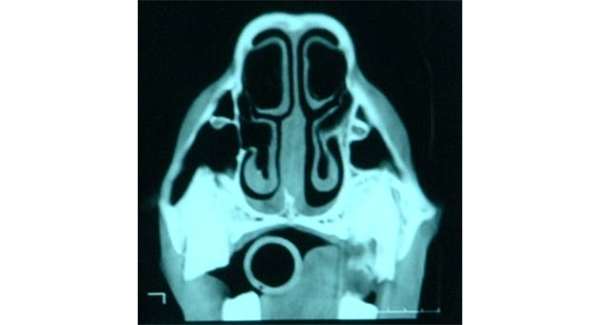

What is being indicated in these images?

Conchal bullae —> air filled but can become infected

then form dorsal & ventral conchae